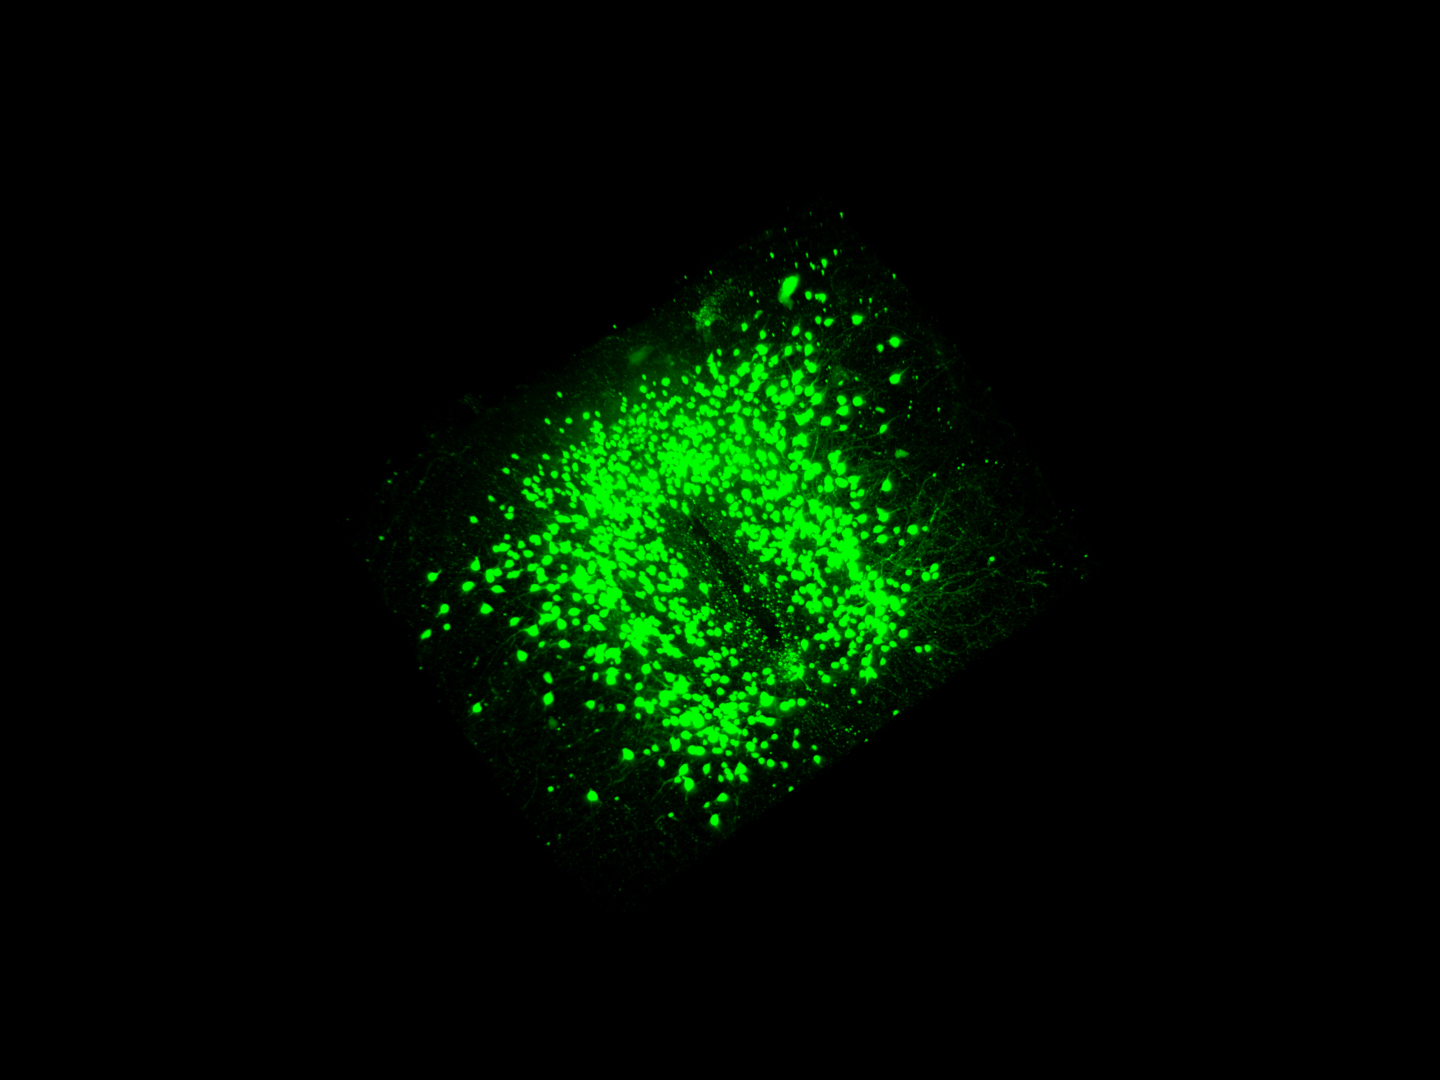

"Es ist uns nun gelungen, verschiedene Subtypen von Nervenzellen in Mäusen auf genetischer Ebene sichtbar zu machen und damit genauer zu untersuchen", sagt Nasim Biglari. "Mit diesem neuen, genetischen Ansatz konnten wir erstmals zwei verschiedene Subtypen von POMC-Neuronen im Detail beschreiben. Unsere Ergebnisse zeigen zum Beispiel eine unterschiedliche Verteilung der beiden Subtypen innerhalb der gleichen spezifischen Hirnregion. Außerdem nehmen sie unterschiedliche Hormone für den Energiezustand des Körpers wahr. Die beiden Subtypen wirken sogar unterschiedlich auf die Nahrungsaufnahme, wobei ein Teil der POMC-Neuronen den Appetit stärker unterdrückt als der andere." Wegen des Einflusses der POMC-Neuronen auf den Stoffwechsel und die Nahrungsaufnahme könnten diese Beobachtungen auch für Krankheiten wie Fettleibigkeit und Diabetes relevant sein.